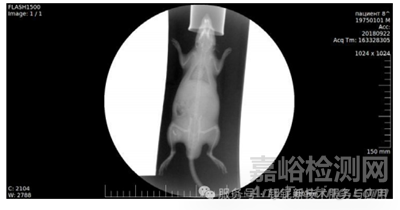

納米顆粒實(shí)驗(yàn): 稀土TaO?微粉制備納米顆粒(粒徑約 20 nm,圖 16),5% 混懸液皮下 / 肌內(nèi)注射大鼠,觀察 8 天內(nèi)的局部對(duì)比度與組織反應(yīng)(圖 17 - 圖 21)。

大鼠皮下注射實(shí)驗(yàn)顯示,5%納米混懸液在45分鐘內(nèi)形成清晰不透射線區(qū)域,8 天后仍可檢測到顆粒沉積,且無紅腫、纖維化等炎癥反應(yīng)(圖18-圖21)。

圖18.皮下給藥后45-60分鐘的登記。